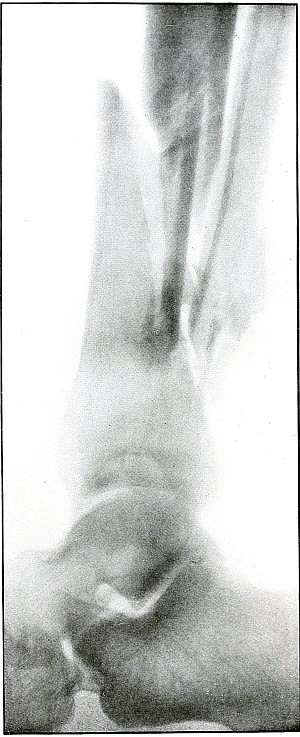

Plate 47.

[Pg 105]

Rifle—Plate 47.

LOWER EXTREMITY.

Gunshot Wound of the Gluteal Region,

with Lodgment of the Bullet Near the Ischium.

Wound of entrance, over gluteal prominence on a transverse line

through the great trochanter.

Wound of exit, none.

There was no bone injury in this case. The bullet, to have lodged in

the soft parts after relatively slight penetration, must have struck

the body at extreme range when its energy was almost spent in flight,

for its normal outline indicates that it was not retarded by ricochet.

The long axis is almost perpendicular to the plate. As the posterior

pelvis was next to the plate, the fairly dense shadow shows the

projectile was not far from the plate and behind the ischium.

The treatment is conservative; infection in such cases is extremely

rare; and only pain or impaired function after many months of

convalescence justifies operation for removal of the missile.

[Pg 106]